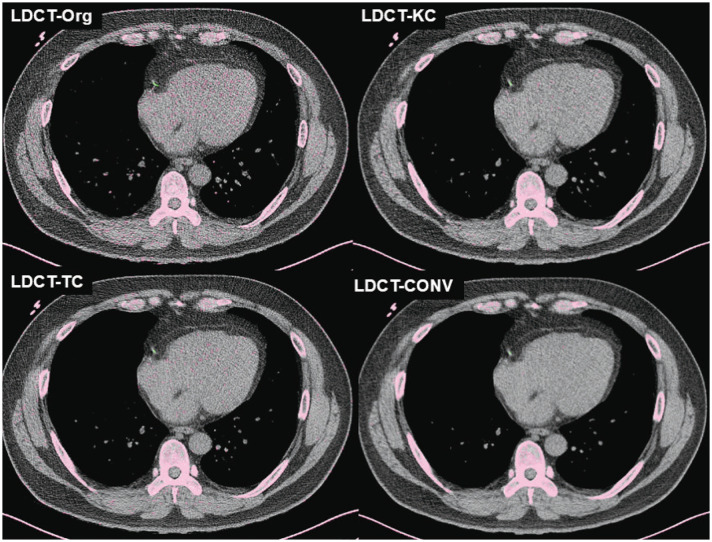

Materials and methods: A total of 225 pairs of LDCT and calcium scoring CT (CSCT) images scanned at 120 kVp and acquired from the same patient within a 6-month interval were retrospectively collected from four institutions. Image conversion was performed for LDCT images using proprietary software programs to simulate conventional CSCT. This process included 1) deep learning-based kernel conversion of low-dose, high-frequency, sharp kernels to simulate standard-dose, low-frequency kernels, and 2) thickness conversion using the raysum method to convert 1-mm or 1.25-mm thickness images to 3-mm thickness. Automated Agaston scoring was conducted on the LDCT scans before (LDCT-Orgauto) and after the image conversion (LDCT-CONVauto). Manual scoring was performed on the CSCT images (CSCTmanual) and used as a reference standard. The accuracy of automated Agaston scores and risk severity categorization based on the automated scoring on LDCT scans was analyzed compared to the reference standard, using the Bland-Altman analysis, concordance correlation coefficient (CCC), and weighted kappa (κ) statistic.